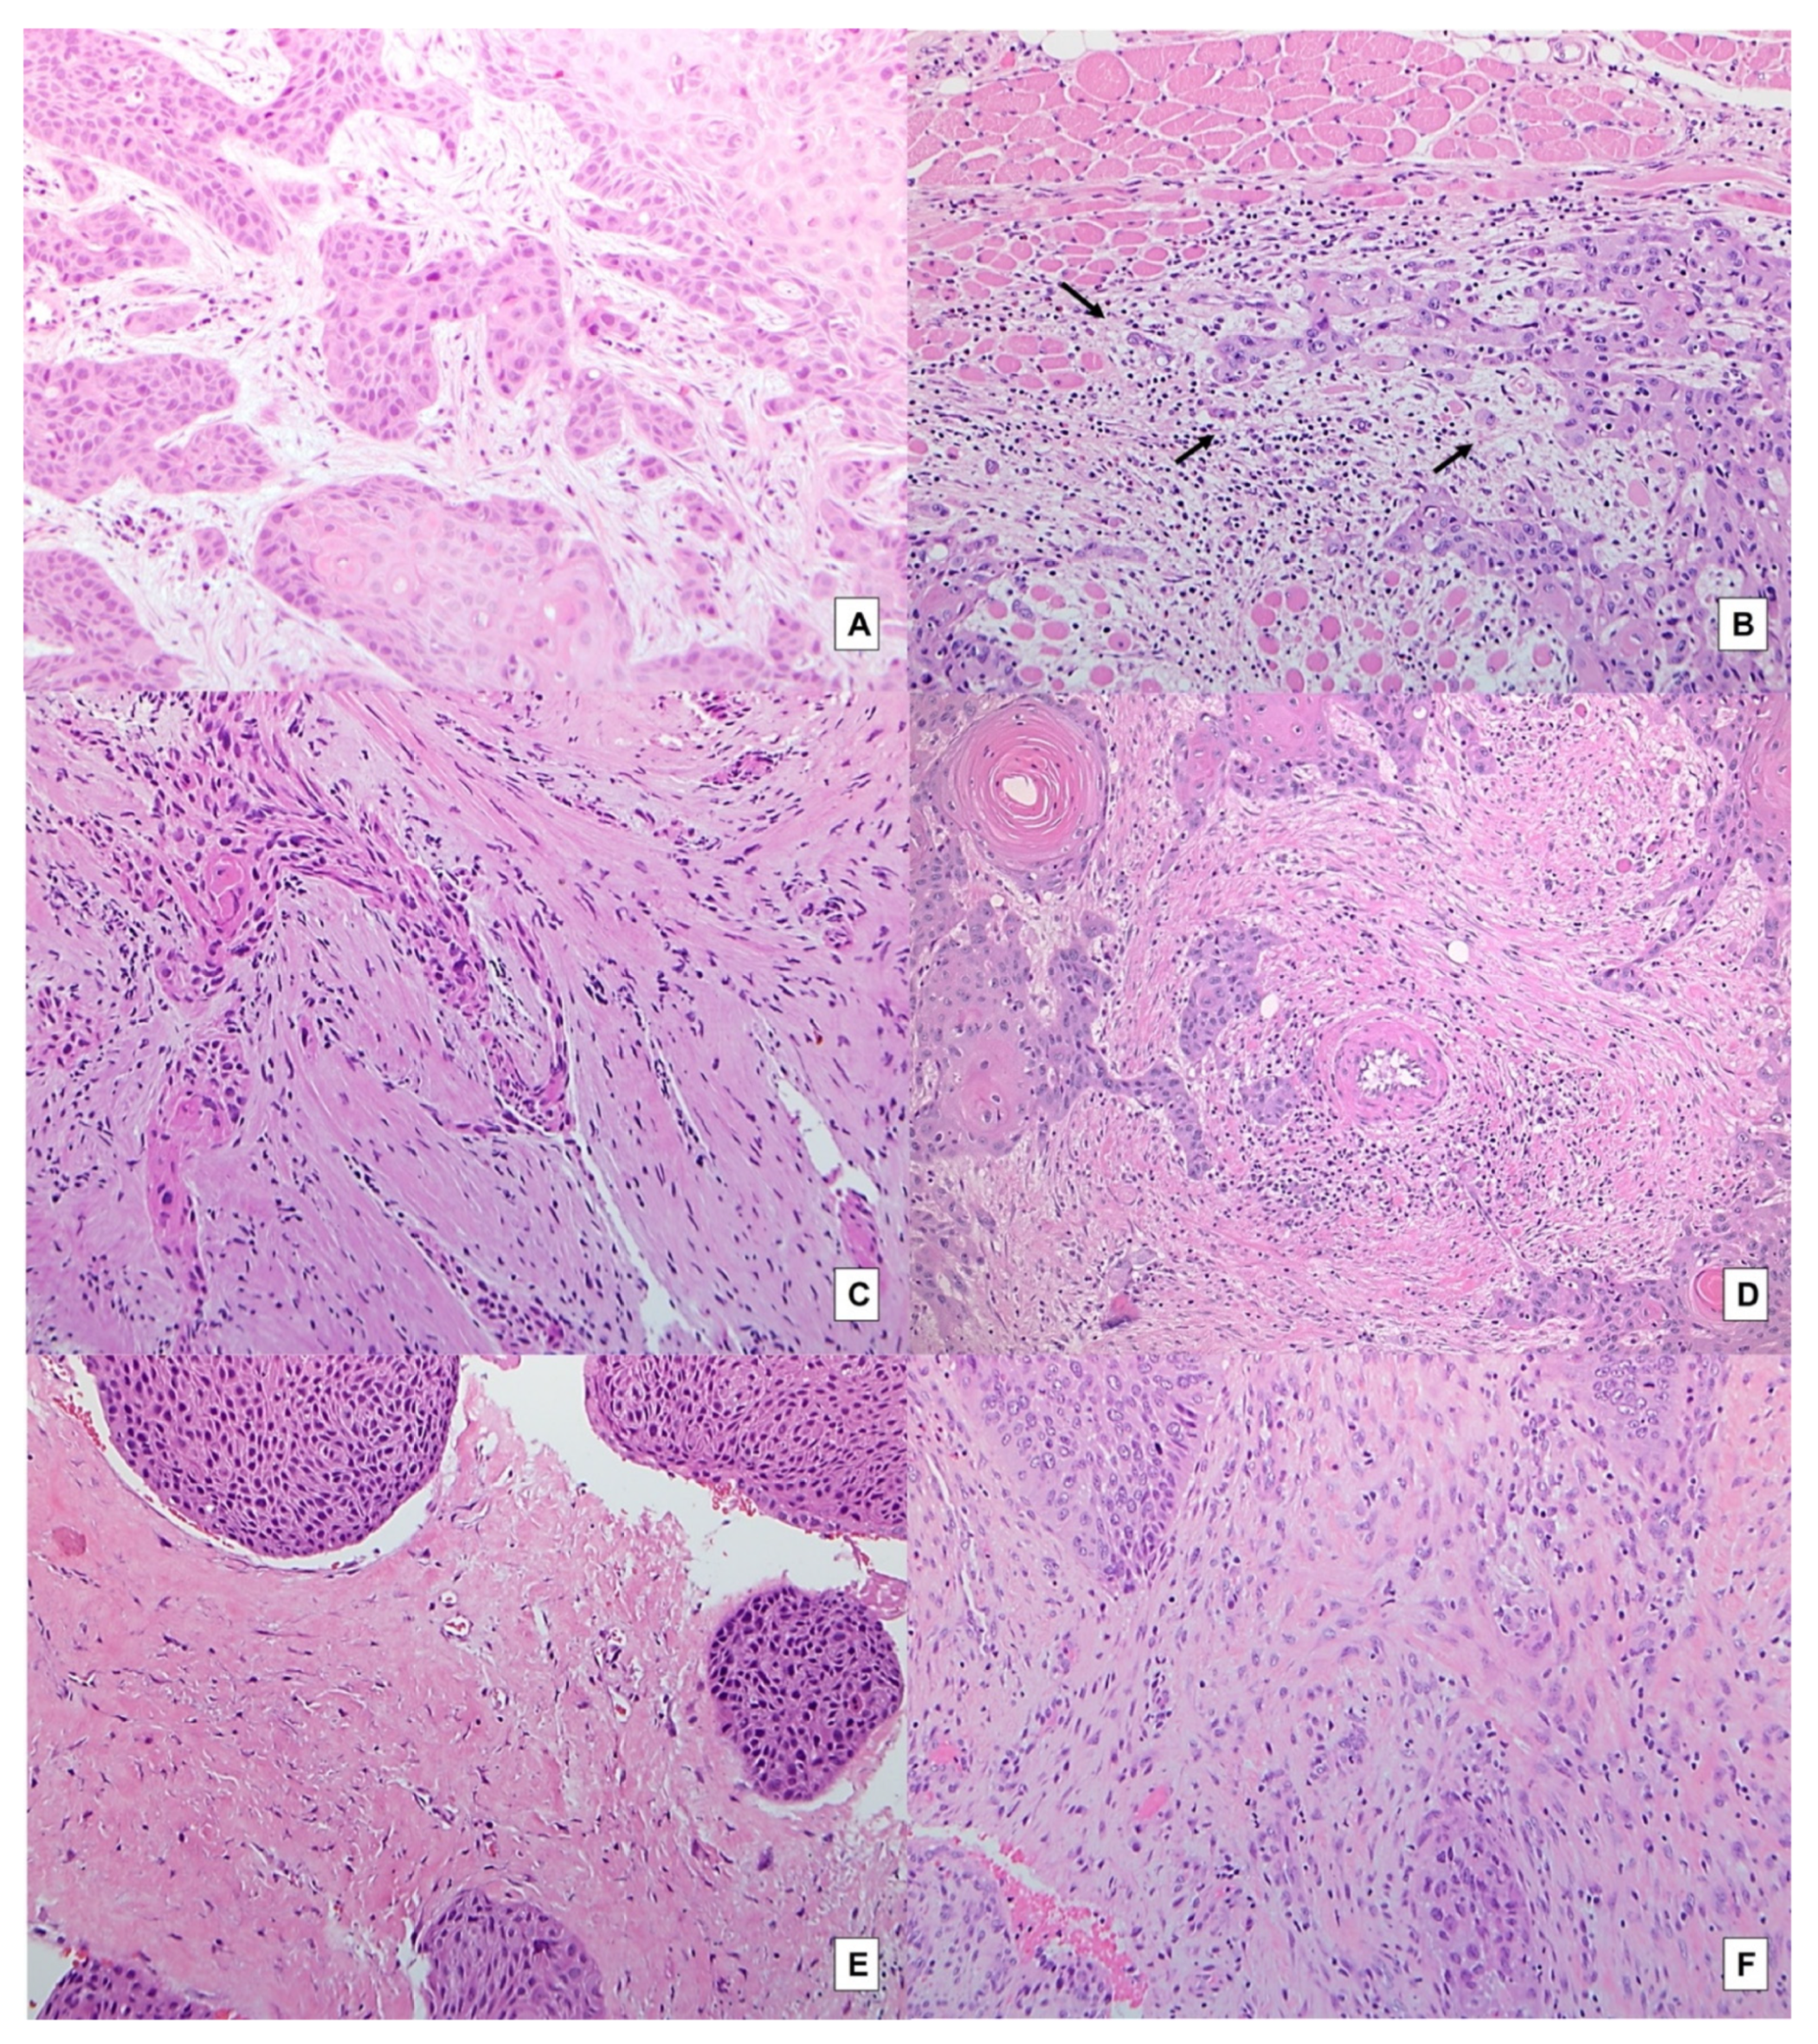

2.1. Overall Outcomes

4.2. Histopathological Investigations